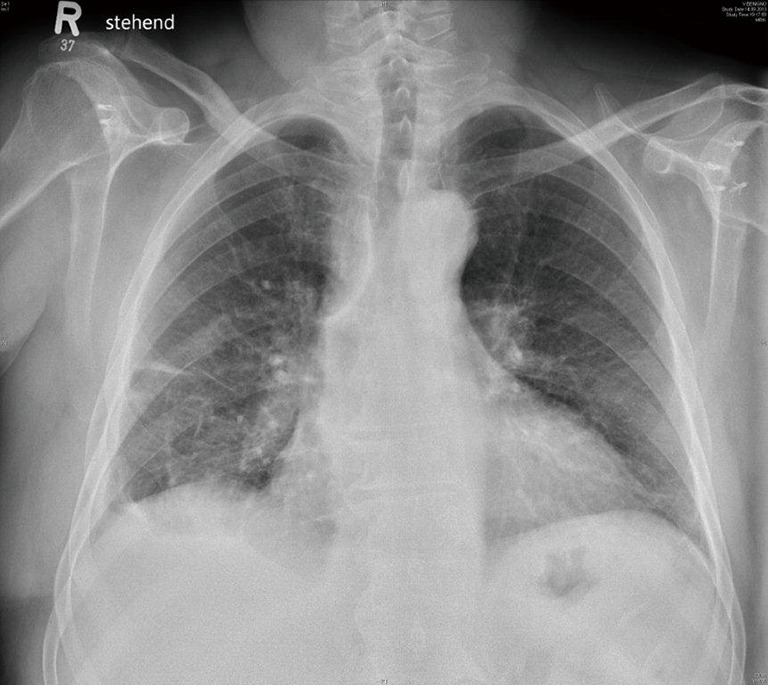

Chest roentgenograms 1 to 3 months postoperatively (Figure 4) were compared with the preoperative roentgenograms (Figure 1) and the radiological improvement was calculated using a 5-point percentage scale according to Casali et al. (5,10). Complete re-expansion (100%) and moderate improvement (75%) were considered as satisfactory results. The radiological estimation was conducted independently by two of the authors (C Caviezel and F Gambazzi) and the mean result of the observations was used for the analysis.

Figure 4.

Chest X-ray of the same patient as in Figures 1-3, performed 6 weeks postoperatively.